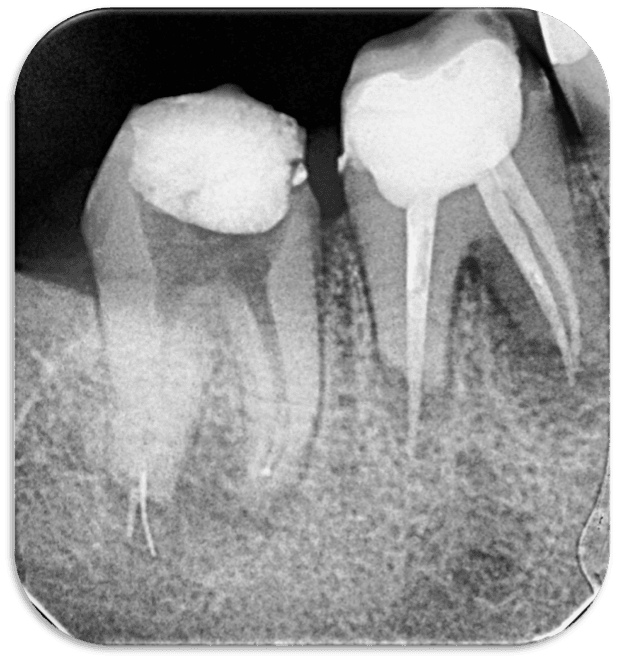

29 yaşındaki sağlıklı erkek hasta kök kanalındaki kırık eğe nedeni ile kliniğimize başvurdu. Yapılan radyografik muayenede distal kanalda apikalden taşkın guta ve kırık alet olduğu tespit edildi (RESİM 1).

RESİM 1: Apikalden taşkın eğe ve guta